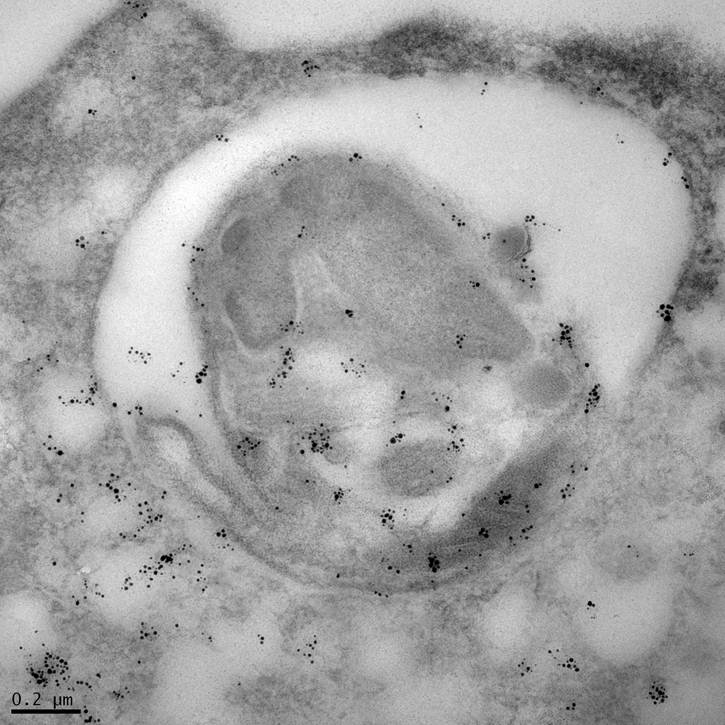

Leishmania Protease GP63 Immunogold Labeling in Human Macrophage

Mary Wilson